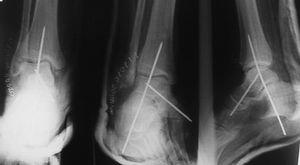

En las fracturas del cuerpo del astrágalo (7 casos) se realizó reducción abierta mediante un abordaje medial con osteotomía del maléolo tibial para visualizar todos los planos de la fractura y fijación interna (RAFI) con tornillos o agujas de Kirschner, o ambos. En 2 casos se realizó un abordaje bilateral debido a la complejidad de la fractura (fig. 6).

Fig. 6. --Fractura abierta de cuello de astrágalo (tipo III de Hawkins) y tratamiento realizado. Radiografías a los 16 meses.

Fig. 6. --Open fracture of the astragalus neck (Hawkins type III) and treatment carried out. Radiographies at 16 months.

En las fracturas del cuello del astrágalo (10 casos) se realizó RAFI con tornillos y agujas de Kirschner. En 4 casos el abordaje fue por vía medial; en 2 fue bilateral (medial y lateral); en 3 se usaron tornillos percutáneos canulados a compresión insertados desde posterior a anterior, y 1 caso en el que se optó por la tracción transcalcánea.